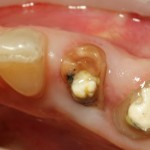

Немедленная имплантация — оптимальное решение в любой клинической ситуации